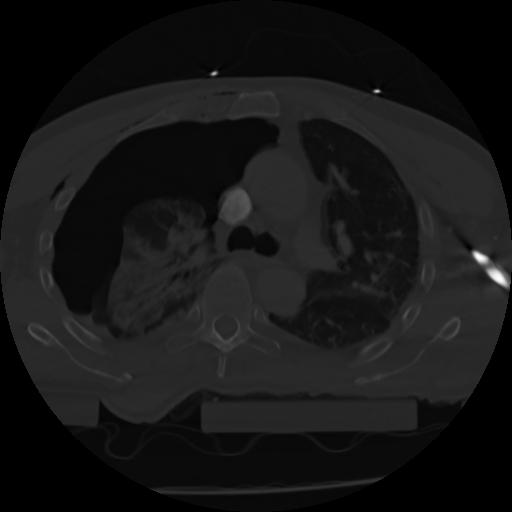

21 ANGIO,CE,Axial,3.0,ANGIO,,